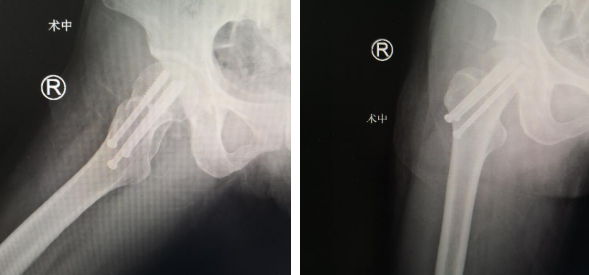

第二天,完善的术前准备后,蒋守海主任陈强张玉帅医生团队为患者进行了机器人辅助下右股骨颈骨折复位内固定手术。术中,先将患者置于牵引床上,经皮克氏针撬拨复位,C型臂透视见骨折端对位良好;接着,机器人导航下定位,设计进针点,随后,机器人的机械臂将手术工具精确定位到手术位置,套筒指向目的钉道的进钉点。手术小组沿着套筒钻入导引针,确认位置无误,再把3枚直径7.3mm空心螺钉通过导引针固定,拔出导针,C型臂见股骨颈骨折对位良好,手术顺利结束。

蒋守海主任说,以往股骨颈骨折如何精准置钉一直是个难题,但在机器人导航辅助下,手术团队将精确度误差控制在0.2毫米以内。整个手术过程中,透视次数大幅减少,对患者及医护人员的放射保护也大大增强。